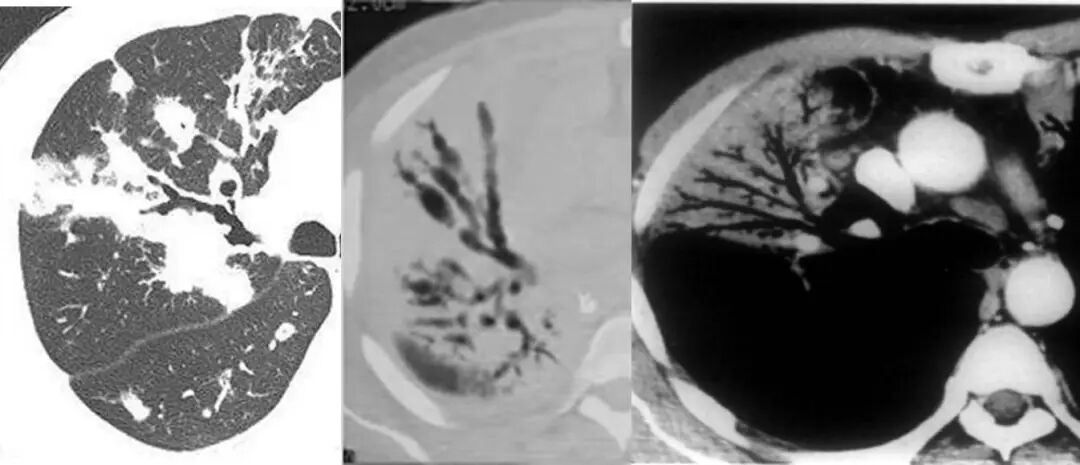

MALT 的支气管扩张并无支气管管壁的破坏。由于淋巴瘤组织浸润导致肺泡塌陷,支气管周围实质破坏造成的,这类支气管扩张在肿瘤治疗后有时可消失。

肺粘膜相关淋巴瘤

结节、肿块,边缘模糊

充气支气管粗大、扭曲

▼伴有空气支气管征充气的支气管粗大、扭曲;